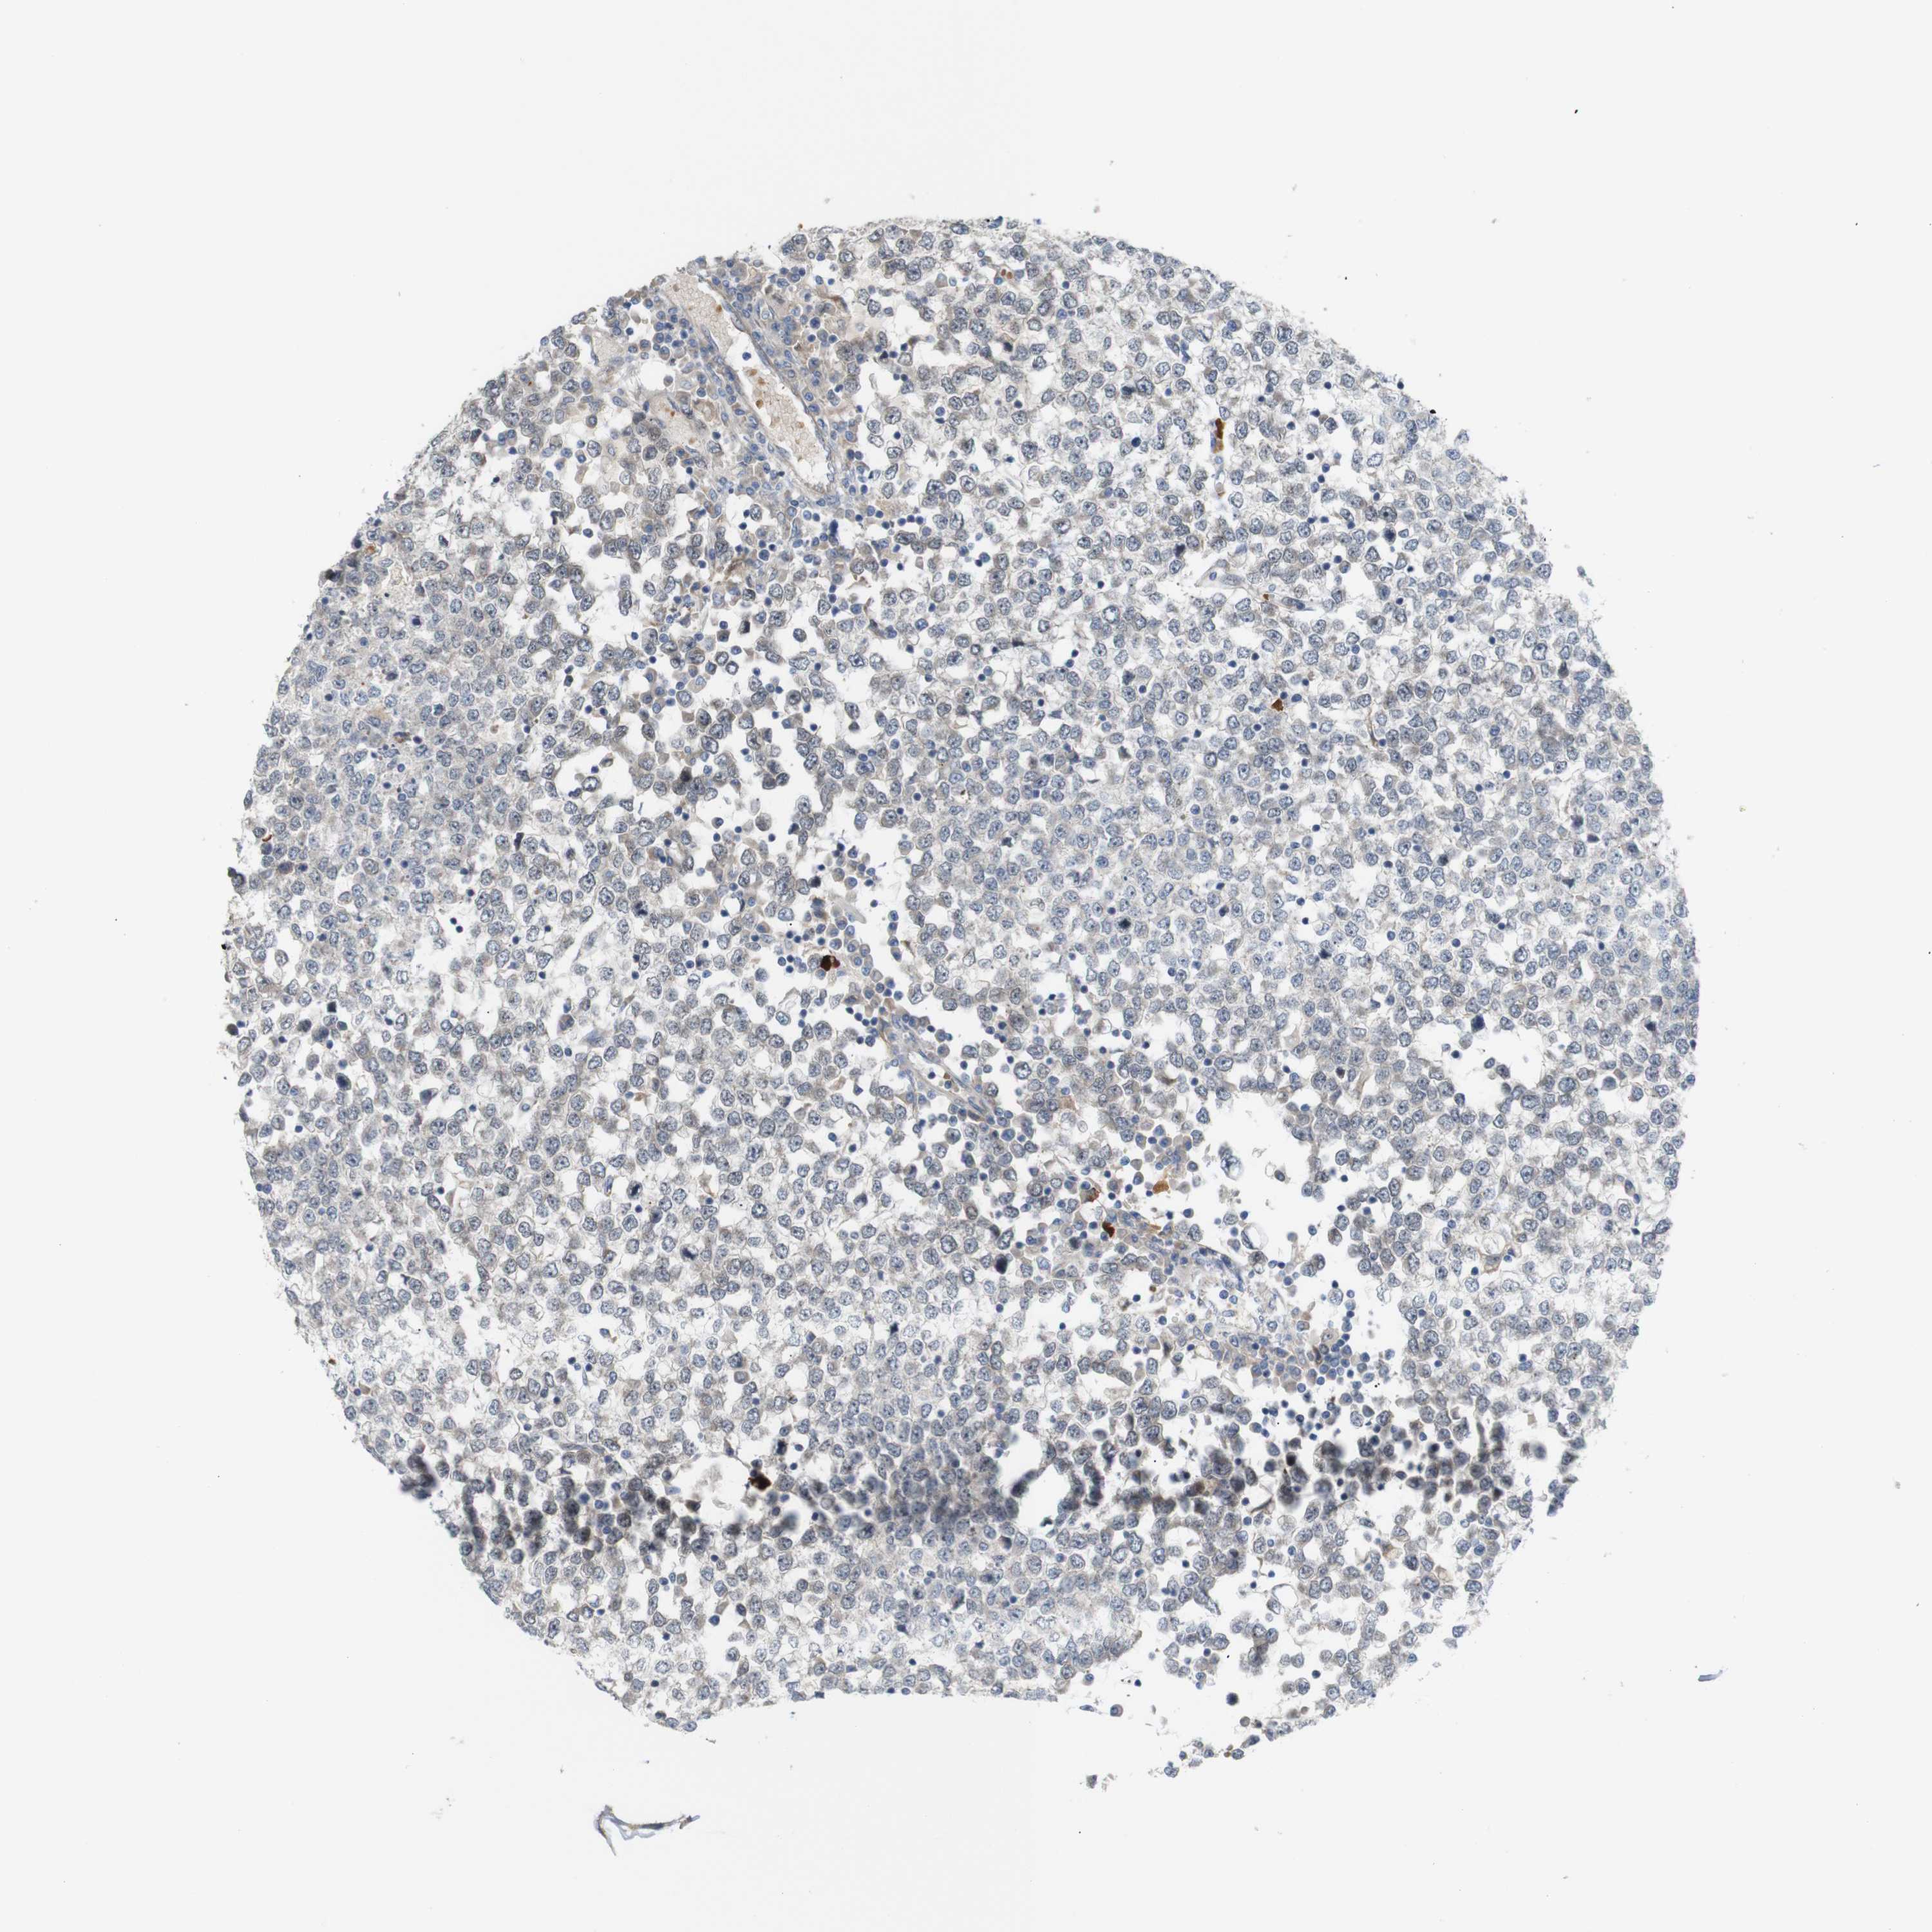

TESTIS CANCER - Protein expressioni

A mouse-over function shows sample information and annotation data. Click on an image to view it in a full screen mode. Samples can be filtered based on level of antibody staining by selecting one or several of the following categories: high, medium, low and not detected. The assay and annotation is described here.

Note that samples used for immunohistochemistry by the Human Protein Atlas do not correspond to samples in the TCGA dataset.

Antibody stainingi

Antibody staining in the annotated cell types in the current human tissue is reported as not detected, low, medium, or high, based on conventional immunohistochemistry profiling in selected tissues. This score is based on the combination of the staining intensity and fraction of stained cells.

Each image is clickable and will lead to virtual microscopy that enables deeper exploration of all samples and also displays staining intensity scores, fraction scores and subcellular localization as well as patient and tissue information for each sample.

Antibody CAB013514

Staining

High

Medium

Low

Not detected

Intensity

Strong

Moderate

Weak

Negative

Quantity

>75%

75%-25%

<25%

None

Location

Nuclear

Cytoplasmic/membranous

Cytoplasmic/membranous,nuclear

Carcinoma, Embryonal, NOS

Seminoma, NOS